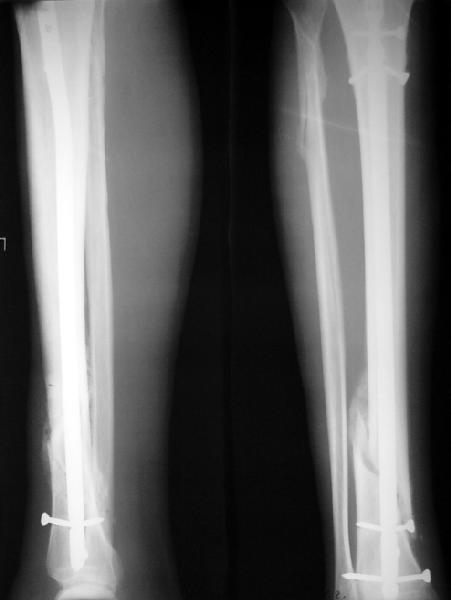

На мой взгляд, на снимках, приведённых Вами - неправильно сростающийся перелом дистальной трети большеберцовой кости, состояние после остеосинтеза интрамедуллярным гвоздём.

Как Вы пишите снимок под номером 1 - менсяц после операции, под номером 2- два месяца после операции.

I think that the X-Rays show S/P IMN of Spiral # of the Distal Tibia consoles in misalignment.

You wrote that a picture number 1 - f month after the surgery, and number 2-two months after the surgery.

Ok. А также и следующий, в 3 месяца.

Это наглядная демонстрация возможности ранней полной нагрузки при нестабильном по оси повреждении, причем не в самых благоприятных механических условиях - при плохом сопоставлении, со слабым фиксатором.